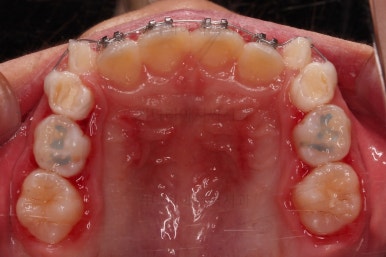

위턱뼈가 가로로 넓어지니 앞니 사이에도 공간이 많이 생겼네요.

부분적으로 교정장치를 부착해서 당사자가 제일 고치고 싶어햇던 앞니 부분을 가지런하게 하기 시작했어요.

충분히 위턱의 성장이 완료되어 페이스마스크 치료는 종료하고 앞니 부분만 좀 더 가지런하게 해주기로 했어요.

총 13개월 걸려서 부산초등학생교정 위턱의 3차원적 성장과 앞니 가지런함을 다 이뤘어요.

앞니의 반대교합 뿐만 아니라 어금니 반대교합도 개선되었네요.